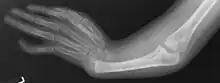

X-ray of arm showing absent radius and radially deviated hand, caused by Thrombocytopenia and Absent Radius syndrome

Duane-radial ray syndrome has two major features that appear in the majority of cases. These two features are Duane anomaly and radial ray malformations. Each feature appears in 65% and 91% of cases respectively.[2]

This is characterized by hand and arm abnormalities. The following are specific characteristics: